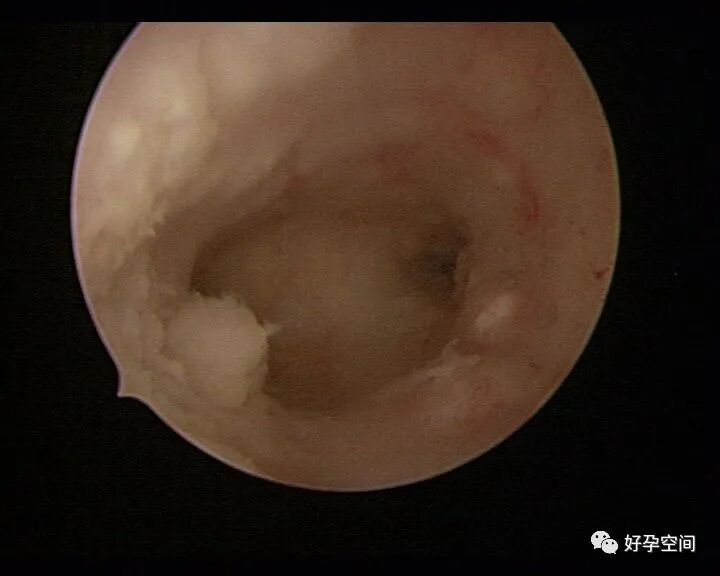

病例14:干酪样坏死溃疡并有灰黄色脓液流出